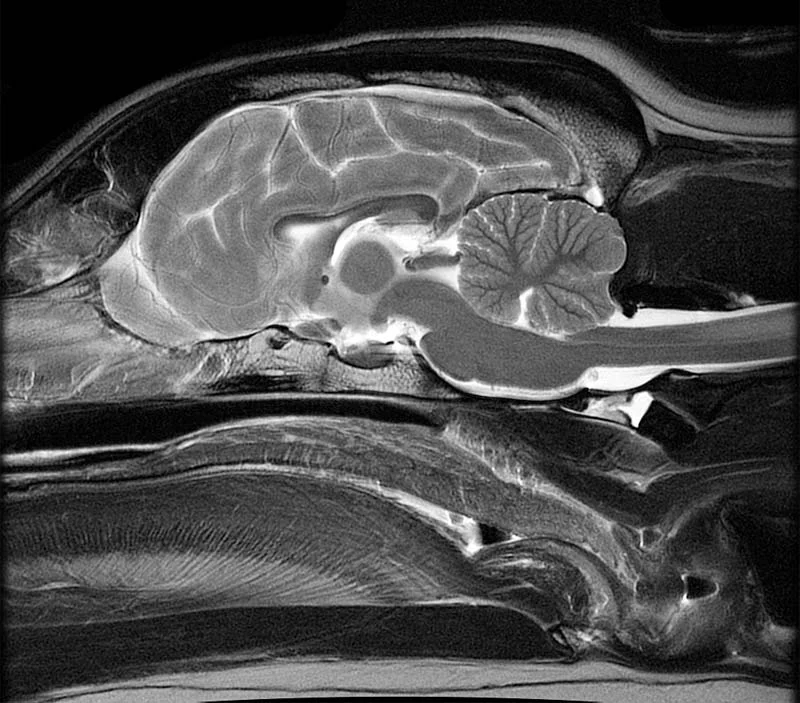

MRI (magnetická rezonance)

MRI je nejlepší pro zobrazení mozku a nervového systému – ukáže například nádory, záněty mozku a mozkových obalů, krvácení, cévní příhody nebo problémy s míchou v oblasti krční páteře. Poskytuje nejdetailnější obraz měkkých tkání, ale vyšetření trvá déle a je dražší než CT.